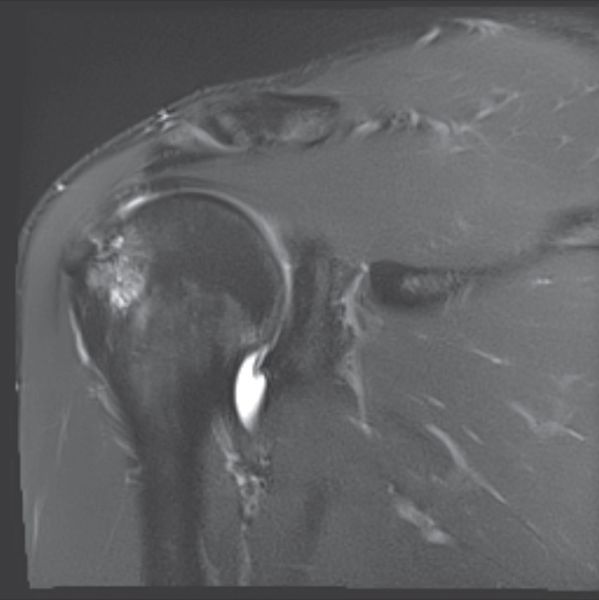

Coronal magnetic resonance arthrography (MRA) view showing bony contusion on the greater tubercle caused by repeated impingement, as well as cysts and a partial-thickness articular rotator cuff lesion.